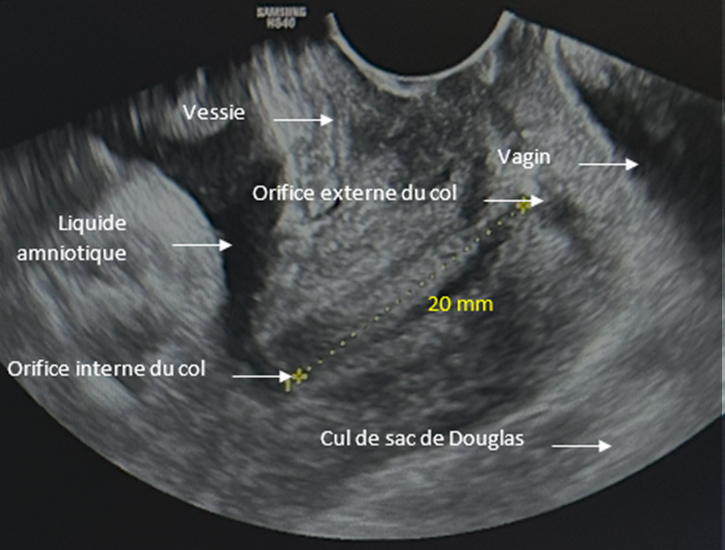

Voici le résultat de la cardiotocométrie et de l’échographie du col réalisée par voie endovaginale.

Figure 4 (Rodolphe Matias de Sousa, La Revue du Praticien)

Figure 5 (Rodolphe Matias de Sousa, La Revue du Praticien)

Au toucher vaginal, le col est mi-long tonique postérieur fermé.

Une menace d’accouchement prématuré se définit comme des contractions utérines régulières et douloureuses (ici 5 par dix minutes visibles à la tocométrie) et un col raccourci ou modifié cliniquement (ici mesuré à 20 mm à l’échographie endovaginale). Un col non modifié est dit long, tonique, postérieur, fermé avec une présentation fœtale non sollicitante.

Concernant l’échographie endovaginale.

Figure 7 (Rodolphe Matias de Sousa, La Revue du Praticien)